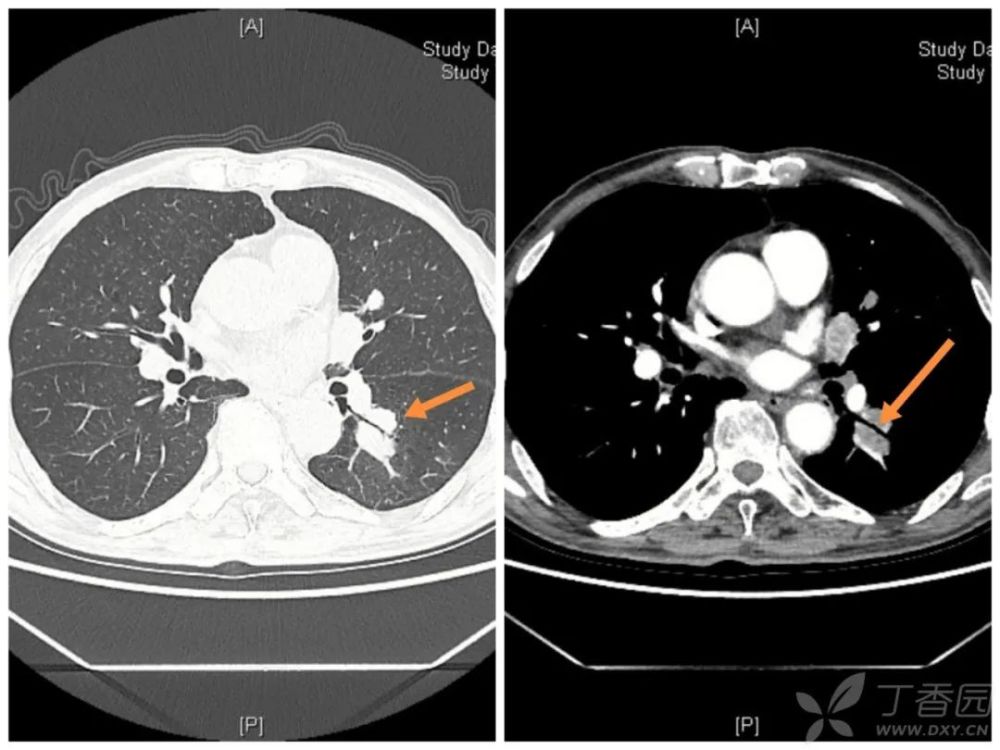

双肺下叶高密度伴充气支气管征象请分析